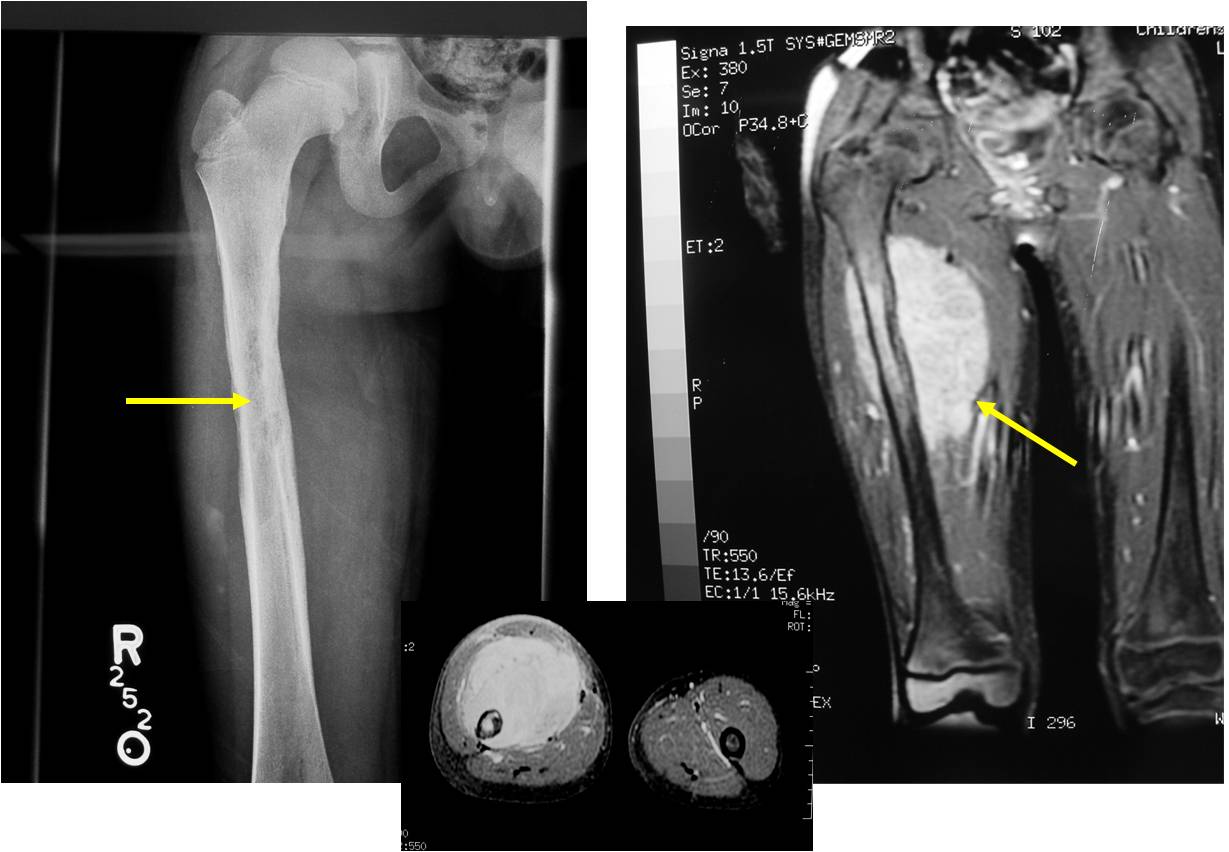

James C. Wittig, MD

0.eosinophilic10a.jpg0.eosinophilic10b.jpg

Эозинофильная гранулёма.

0.ewing7_.jpg

#200 Саркома Юинга? (молодой возраст, выраженный мягкотканный компонент)